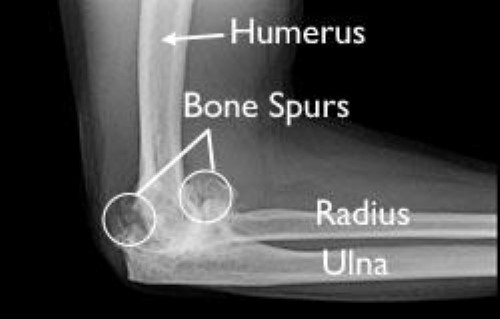

37+ Elbow Bone Spur Surgery Rehab Images. The goal of surgery is to remove the bone spurs to allow for a more normal joint or to remove the pressure on muscles, tendons, ligaments, or. Bone spurs are bony projections that develop along the edges of joints like your elbow.

These bone spurs can form on any bone, but are mostly found forming on the bones of the feet, spine and elbow. Any surgical procedure carries risks, however every effort is made to minimise these to ensure the best possible outcome from your surgery. Bone spurs normally happen on the back of the spine as a person ages. Treatment of elbow spur is dependent on the severity of the condition.